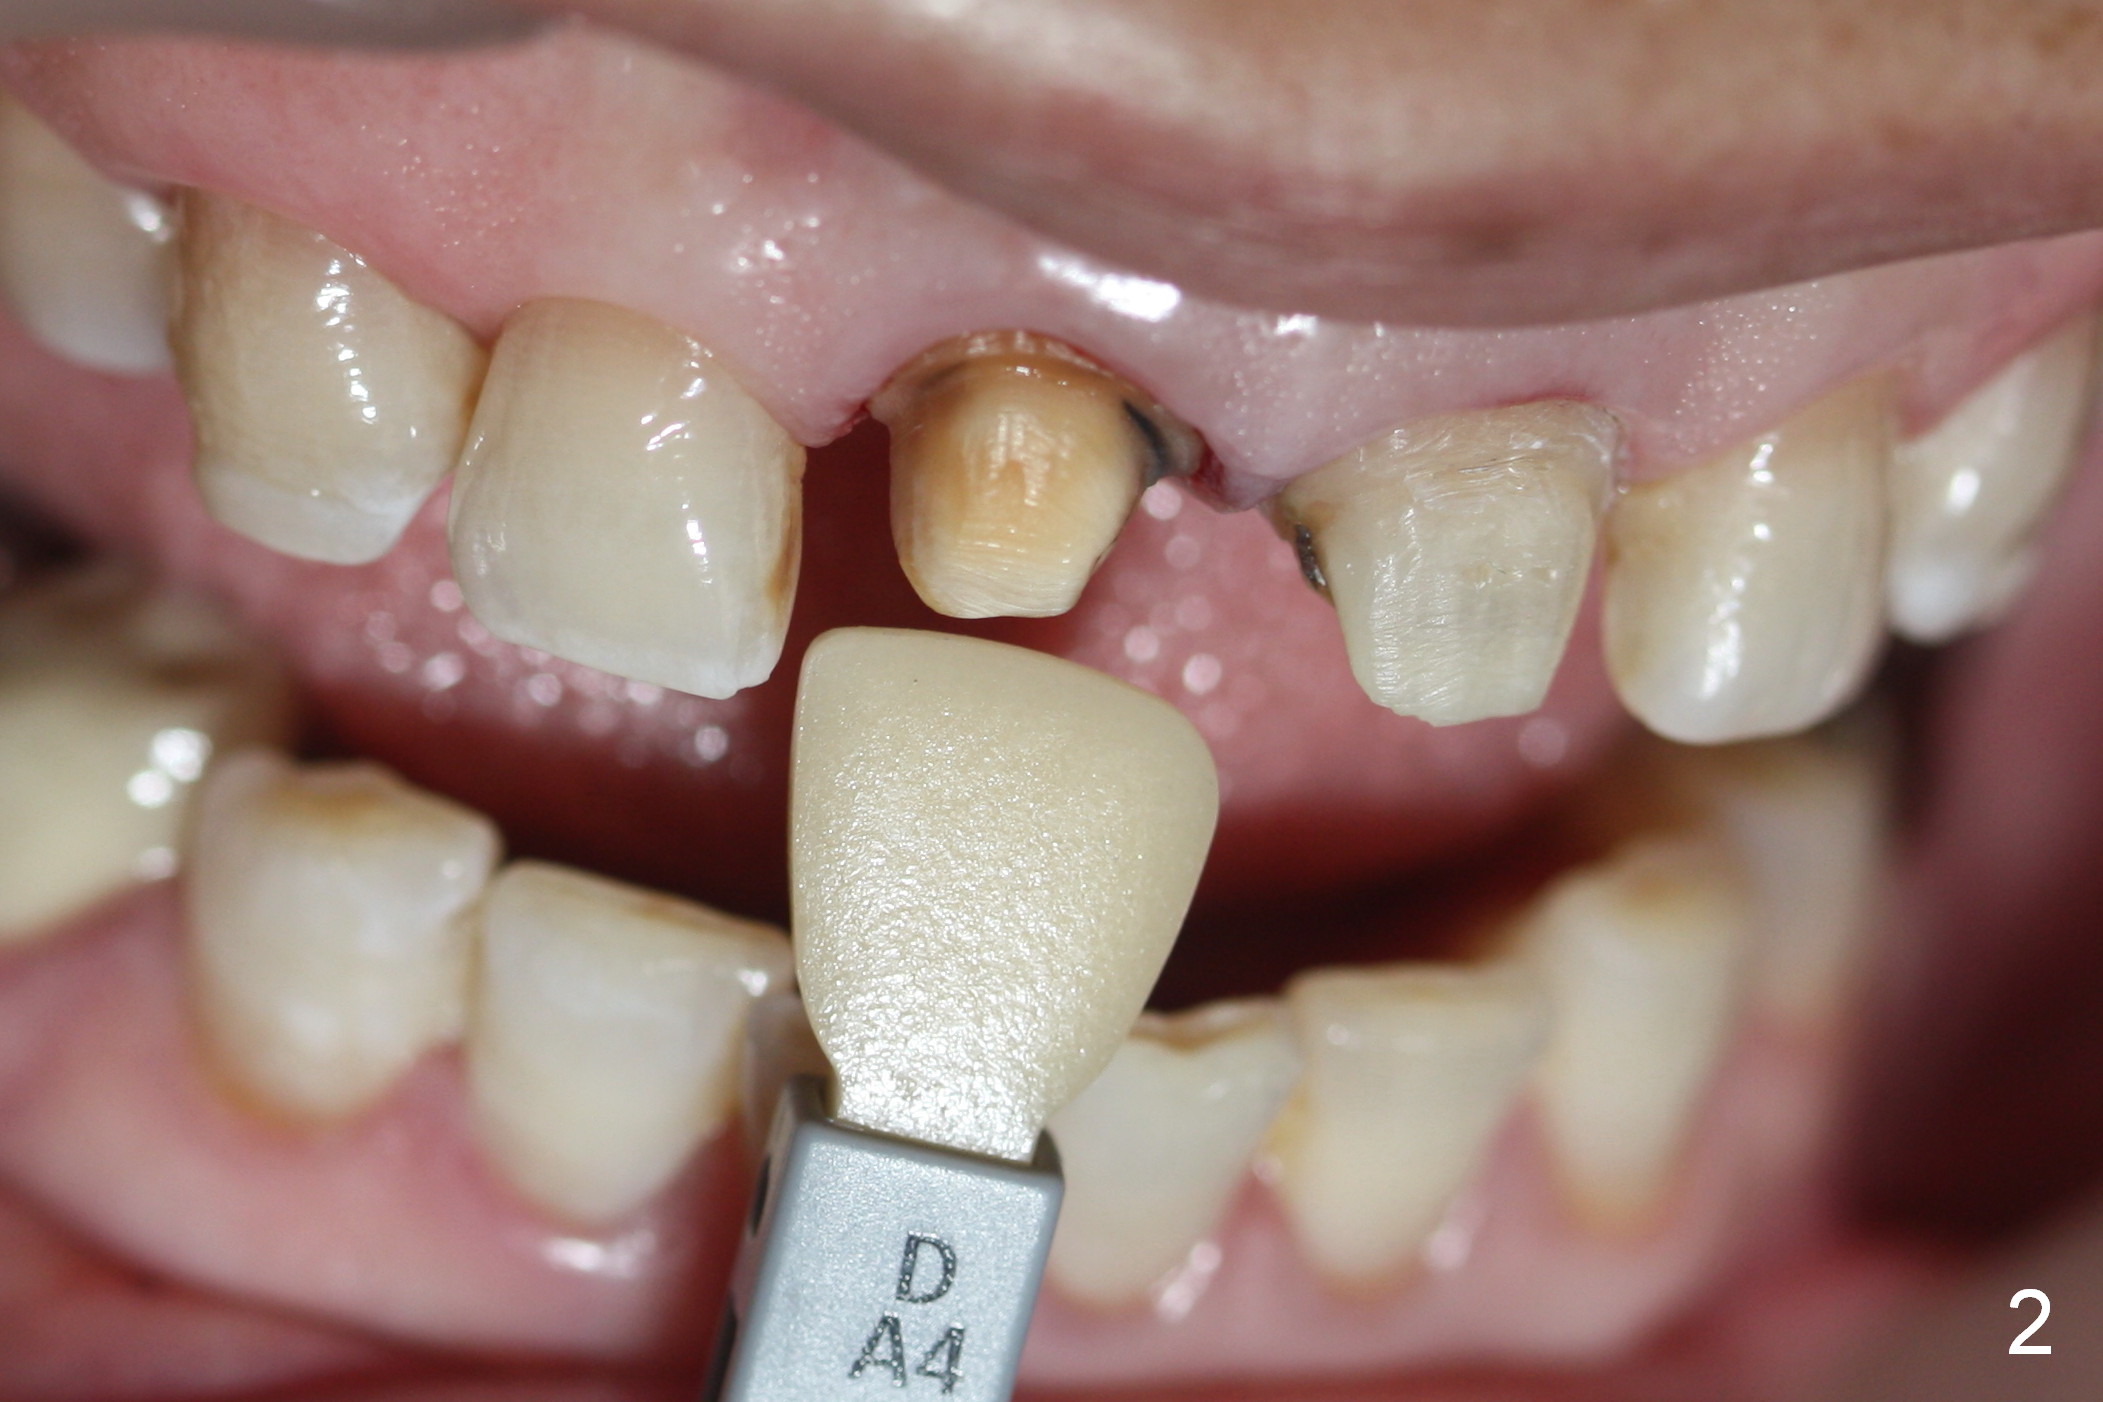

A 54-year-old lady (CL) has a discolored central incisor (#8, Fig.1). Stump shade is shown in Fig.2. Other reference shades are shown in Fig.3-5.